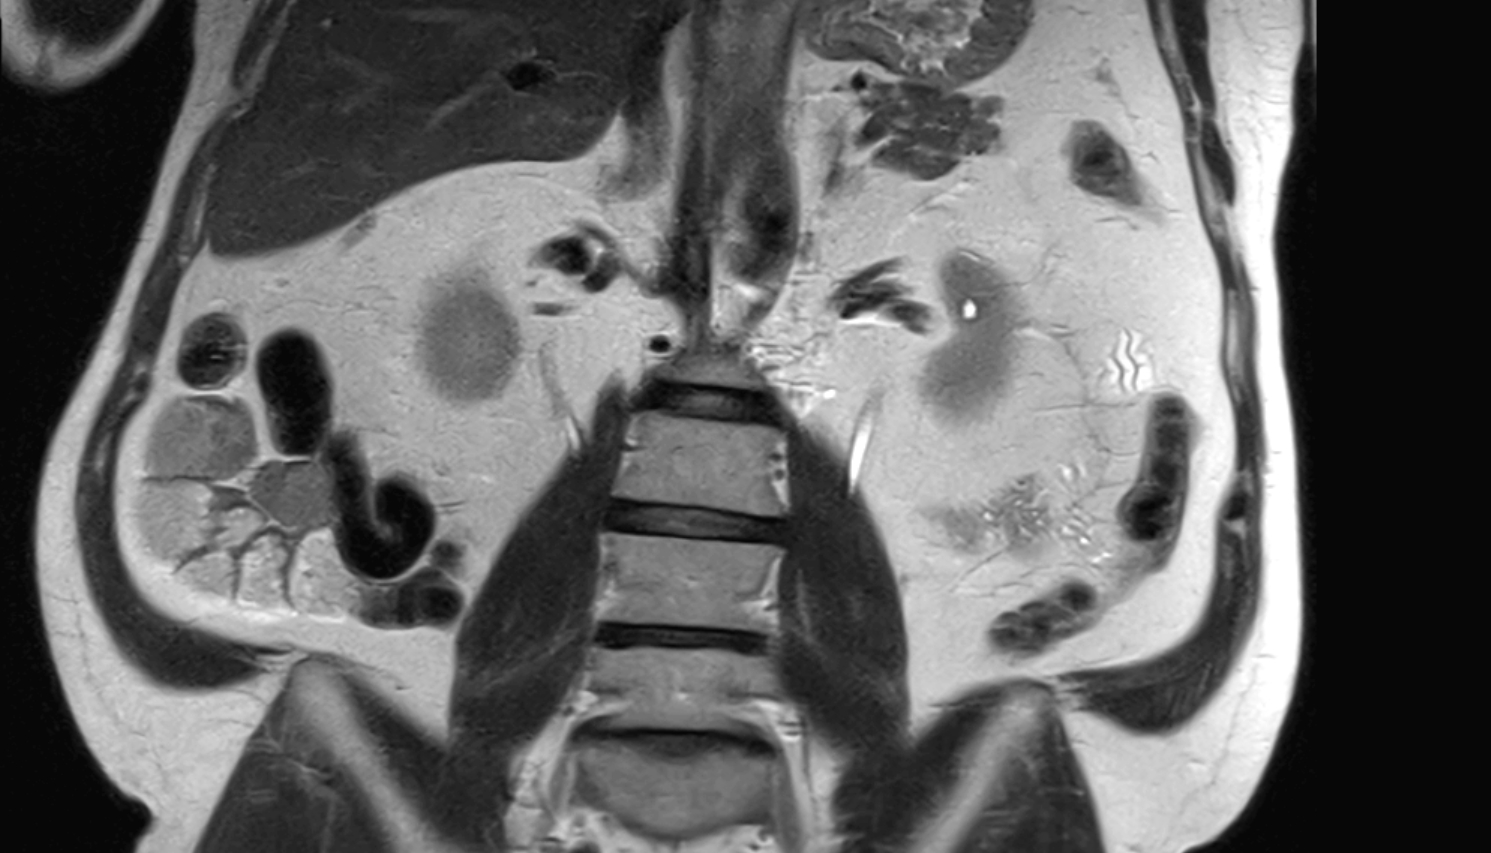

- kidneys

- Right kidney

- Left kidney

- Kidney cortex (Renal cortex)

- Renal medulla

- Renal pyramids

- Ureters

- Renal artery

- Renal vein

- Left renal vein

- Right renal vein